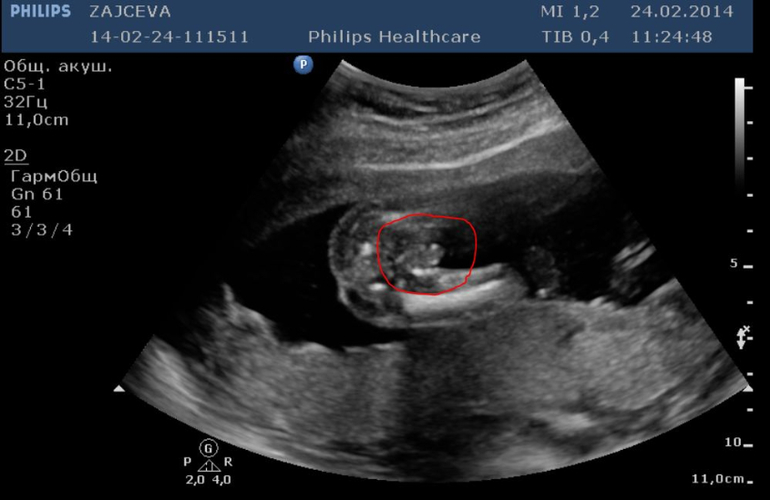

Побежала к Г. Мне подтвердили беременность. Но я волновалась из-за этого 1 дня кровотечения. И вообще не верилось. Поэтому сходила на УЗИ. Там поставили срок 6,5 недель. Показали точечку на мониторе... Дали сердечко послушать... Вот это счастье!

Прекрасные фоточки, мой тоже в прошлом году УЗИ начинал с демонстрации *я мальчик!*